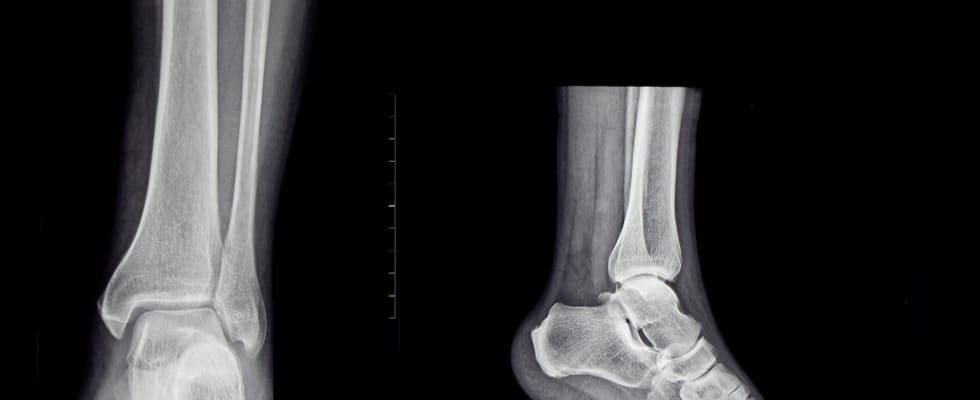

A radiografia do pé é um exame de imagem essencial para diagnosticar e monitorar condições que afetam os ossos, articulações e tecidos adjacentes do pé. Este procedimento é frequentemente solicitado para avaliar dores, deformidades, lesões traumáticas ou progressão de doenças degenerativas e inflamatórias.

O exame de radiografia do pé é fundamental para detectar fraturas, luxações, artrite, osteoporose, alterações na estrutura óssea ou problemas causados por uso inadequado de calçados e prática esportiva. Também é útil para o acompanhamento da evolução de tratamentos ortopédicos ou cirúrgicos, fornecendo informações valiosas sobre a disposição e a recuperação dos ossos.

Durante uma radiografia do pé, o paciente posiciona o pé em um suporte especial enquanto uma pequena quantidade de raios X atravessa a região. Os raios X são absorvidos em diferentes graus pelas diversas estruturas do corpo, criando uma imagem em tons de cinza que mostra ossos e certas estruturas de tecido mole. Este exame é rápido, não invasivo e oferece detalhes críticos para um diagnóstico preciso.